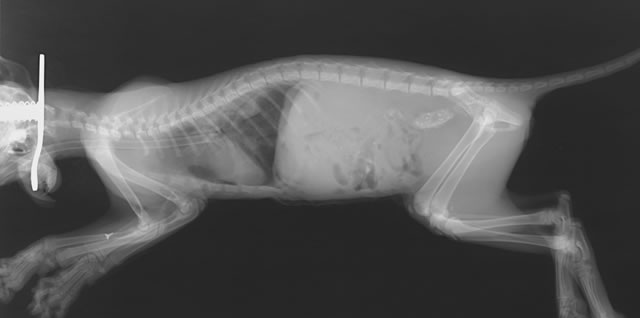

前回の横隔膜ヘルニアの手術直後のレントゲン写真です。 横隔膜のラインもばっちり、各臓器の位置もばっちりです。

ただしこの後も肺に水が溜ま ったり、ショックを起こしたりしないか充分気をつけなければいけません。

横から撮ったレントゲン写真です。黄色のラインは本来あるべき横隔膜のラインです。

本当であればここまで肺が広がり、写 真上で黒く写ってくるはずですが、そのラインが確認できません。

また、肺のあるべき位 置まで腹腔臓器が移動してしまっているのがわかります。

伏せをした状態で撮ったレントゲン写真です。黄色の丸で囲まれた部分が入り込んだ臓器です。

お腹の中の臓器の大部分が胸に入り込ん でしまっているようです。

この写真でもやはり肺の位置まで腹腔内の臓器が入り込んでいるのが確認できます。

撮影の向きを変えることによって横隔膜の右側で横隔膜ヘルニアを起こしていることがわかります。

また、右側の骨盤に一部形の異常があり、骨盤骨折が疑われます。